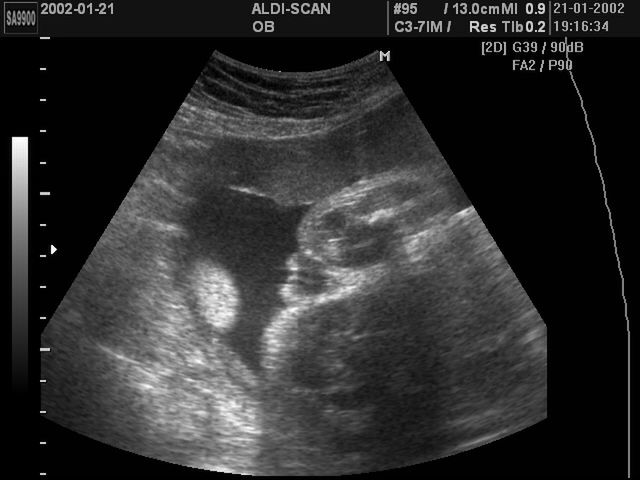

Test PAPP-A wykonuje się między 10., a 14. tygodniem trwania ciąży. Test ten jest badaniem przesiewowym, wykonywanym w celu wyodrębnienia grupy kobiet, których dzieci mają zwiększone ryzyko wystąpienia zespołu Downa, a także zespołu Edwardsa czy zespołu Patau. W skład testu PAPP-A wchodzi badanie biochemiczne krwi matki, dodatkowo wykonywana jest zwykle ocena parametrów ultrasonograficznych płodu.

Kobieta, która chce poddać się testowi PAPP-A, powinna tego samego dnia wykonać badanie krwi oraz uzupełniająco badanie USG płodu. We krwi matki oznacza się poziom białka ciążowego A, czyli PAPP-A, oprócz tego cennym badaniem jest pomiar wolnej podjednostki beta gonadotropiny kosmówkowej – czyli wolnej beta-hCG. Parametr oceniany podczas USG płodu to przezierność karkowa, czyli pomiar warstwy płynu znajdującego się w obrębie tkanki podskórnej szyi płodu.